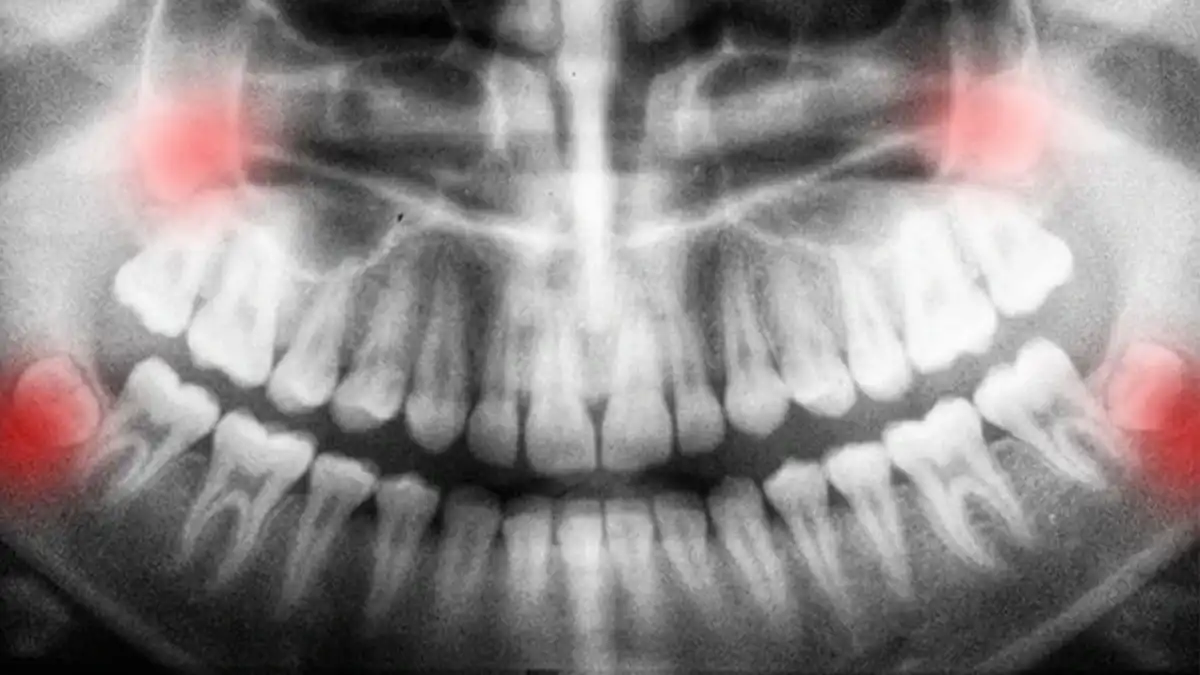

A hard, bony lump on gum tissues—sometimes called a “gum bone spur” or "bone spicule" can come from a few different sources.Wisdom Teeth Removal: Pain, Impacted, Recovery & Cost